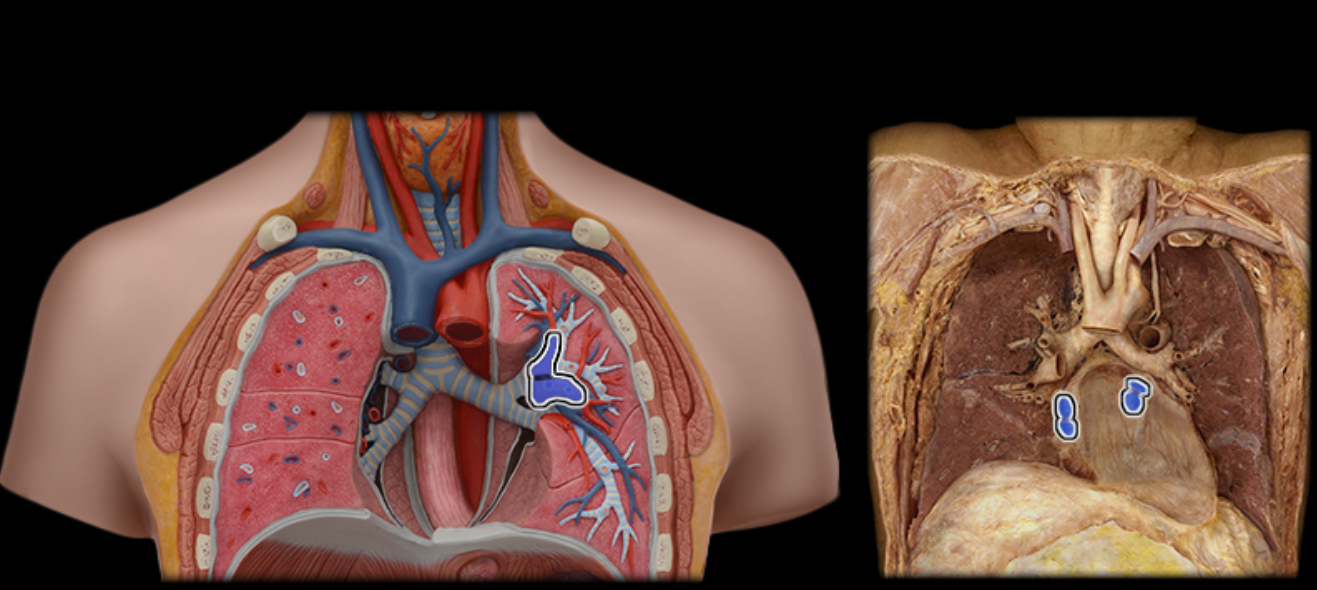

What type of blood is at the location indicated by the arrow?

oxygenated blood of the systemic circuit

Pulmonary a.

Pulmonary vv.